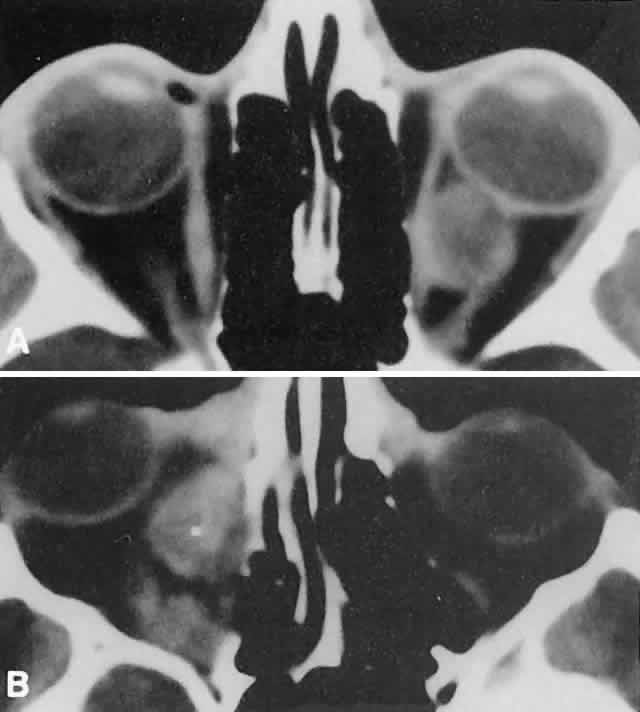

In dacryoadenitis, external inflammatory signs are localized to the superotemporal quadrant, and CT shows enlargement of the lacrimal gland (Fig. 24). Lacrimal gland inflammation may be bacterial, viral, or a variant of IIPT. It is possible, however, that many cases of “idiopathic” dacryoadenitis represent unidentified viral infections. In bacterial dacryoadenitis, a leukocytosis with a left shift may be present.96 In questionable cases, a 1-week course of oral antibiotics can be administered to these patients. Among children, the probability that an enlarged lacrimal gland represents neoplasia rather than inflammation is lower than among adults, although epithelial lacrimal gland tumors occasionally may occur in the pediatric population and can produce external inflammatory signs. If the general signs and symptoms of IIPT are lacking, a biopsy should be performed.

Fig. 24. A. Nonbacterial dacryoadenitis may be unilateral or bilateral. External inflammatory signs are maximal in the superotemporal quadrant. B. The left lacrimal gland is enlarged, with a shape molded by the globe and orbital walls. A neoplasm usually can be ruled out by analysis of the history, CT findings, and echographic characteristics, but a biopsy may be required in equivocal cases.